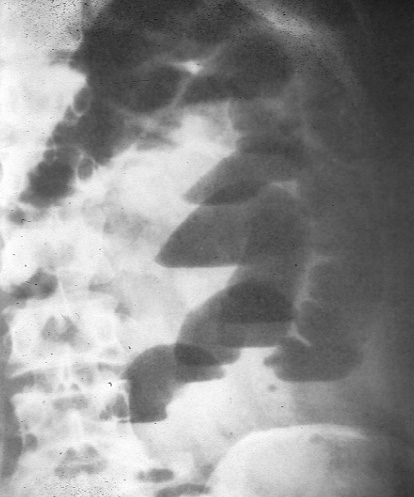

air-fluid level ใน obstruction มักจะมีระดับต่างกันภายใน loop เดียวกัน (ดังรูป a24)

รูป a24

ลำไส้เล็กอุดตัน เนื่องจากพังผืดจากบาดแผลและกระสุนปืน